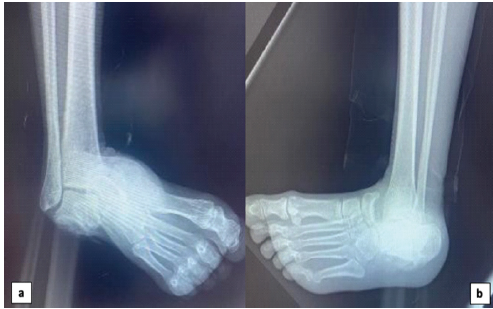

Distal vascular examination showed palpable posterior and anterior tibial pulses. Sensory and motor function of the toes were preserved. Standard anteroposterior and lateral radiographs of the ankle demonstrated a medial peritalar dislocation (Fig. 2).

Figure 2: Preoperative radiographs of the right foot. (a) Standard anteroposterior and (b) lateral radiographs demonstrating isolated medial peritalar dislocation without associated fractures.